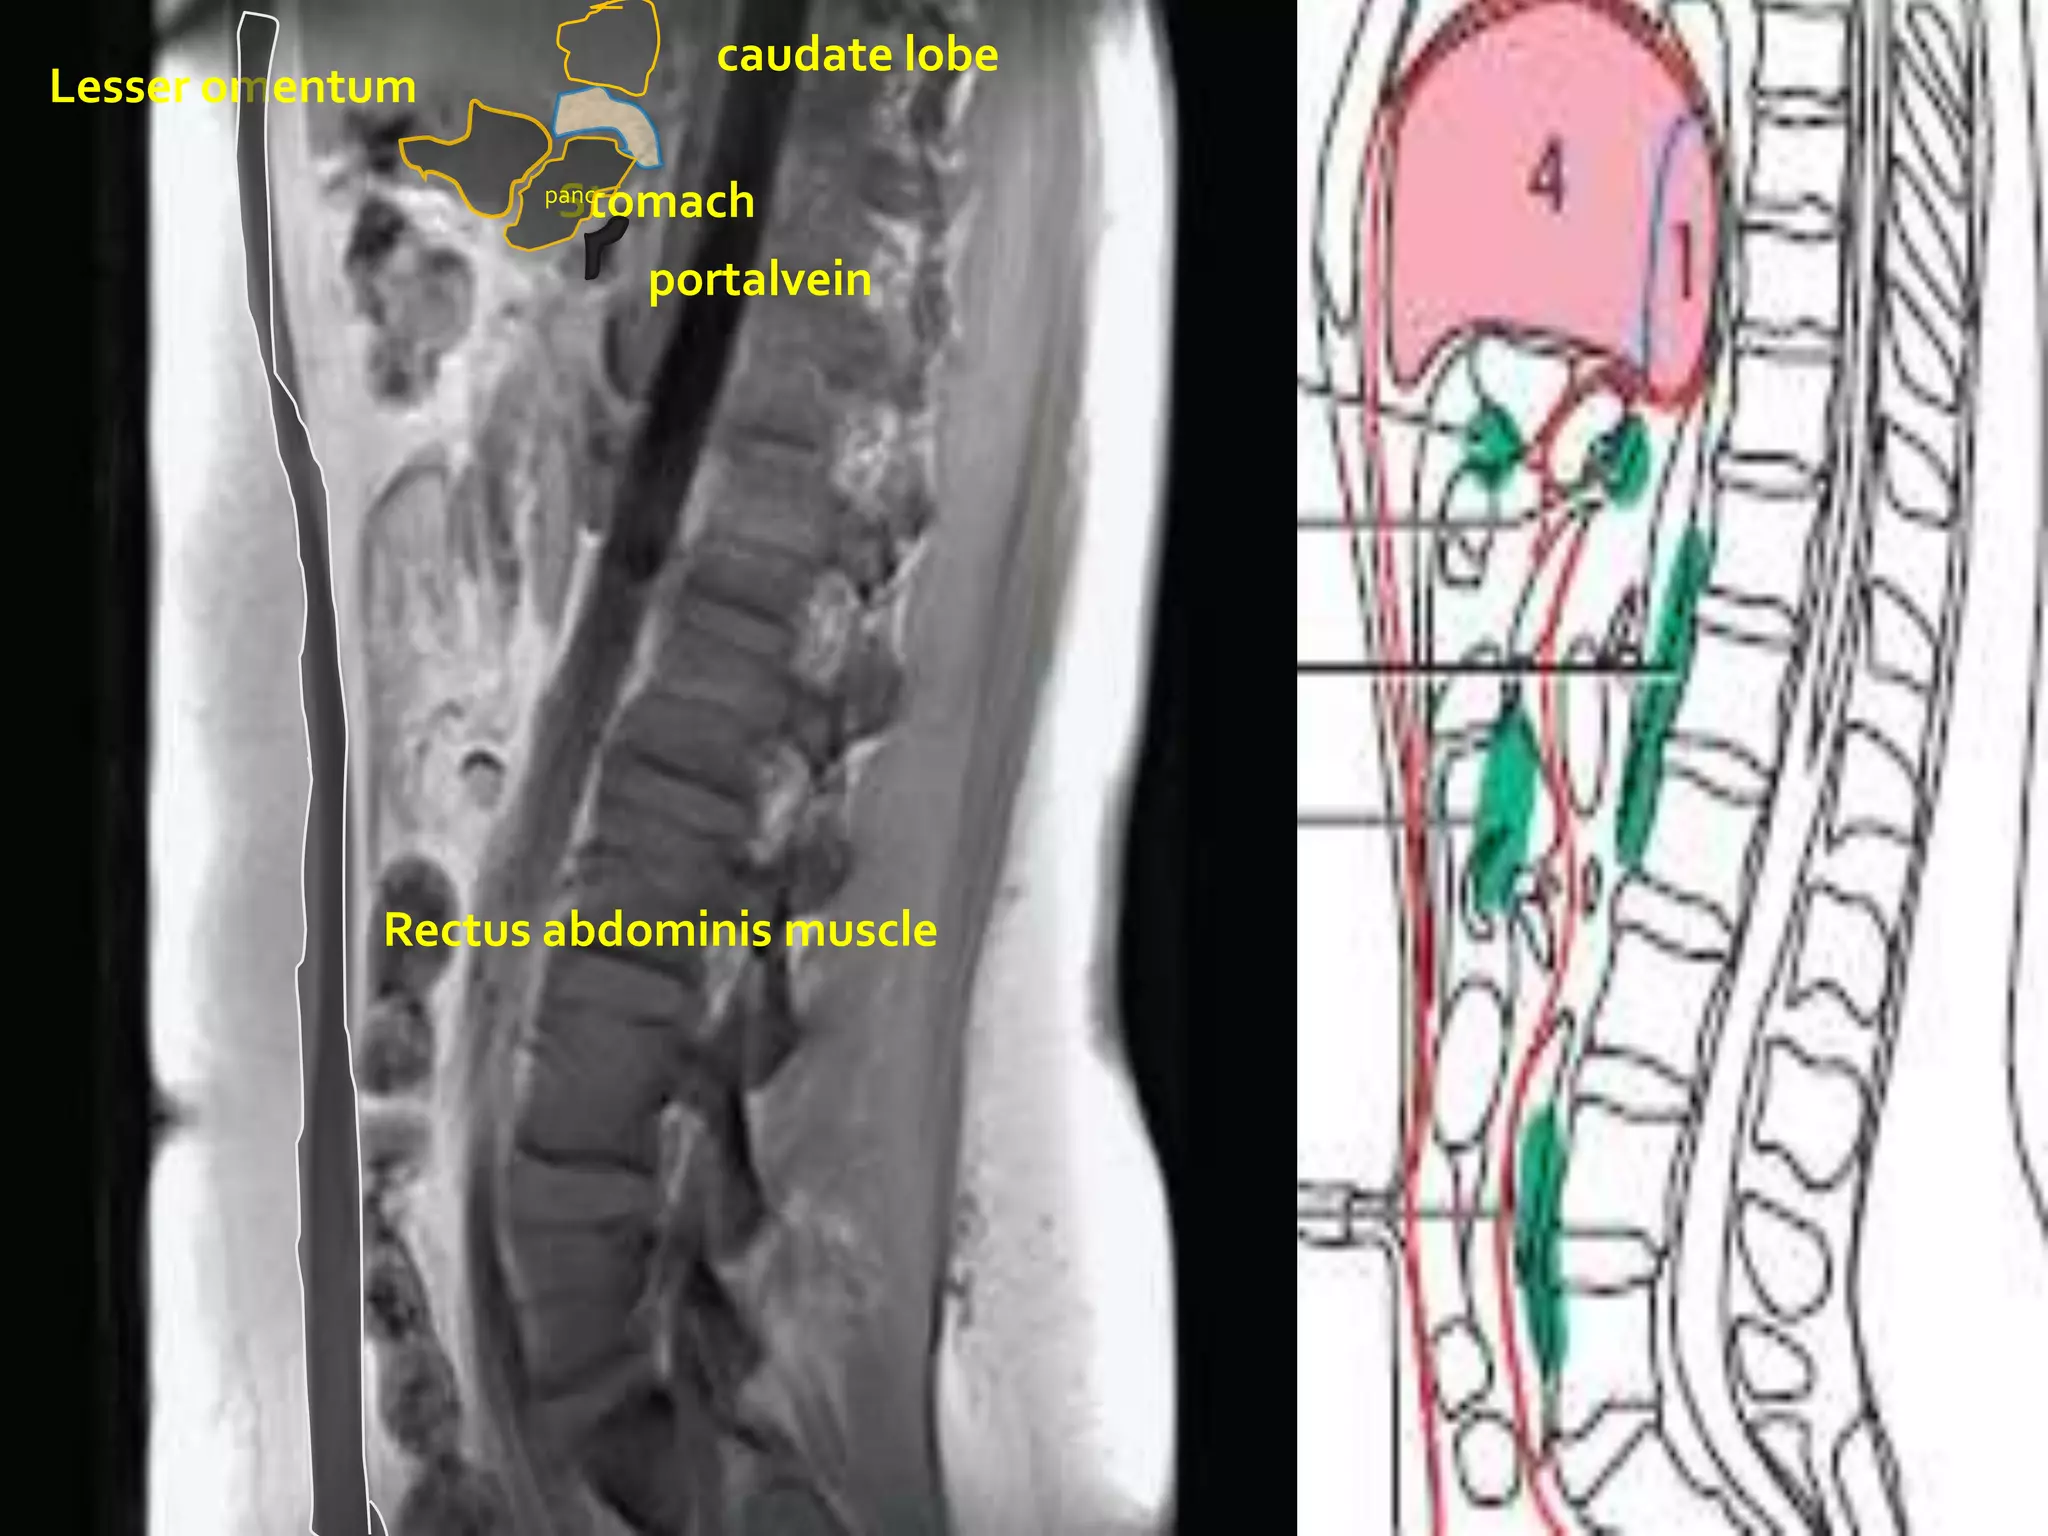

caudate lobe

Lesser omentum

Stomach

panc

portalvein

Rectus abdominis muscle